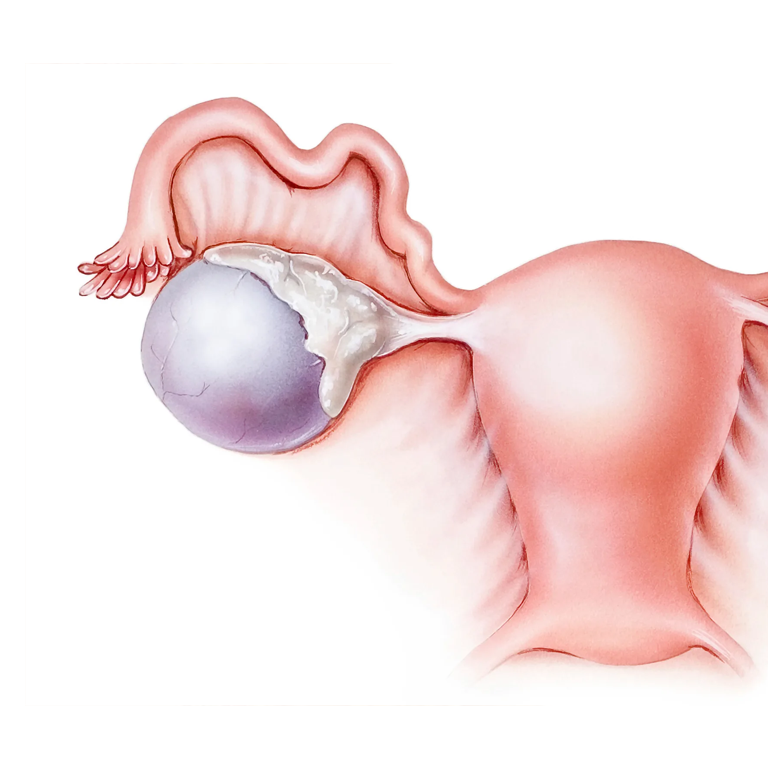

Гистологические изображения фолликулярной кисты яичника